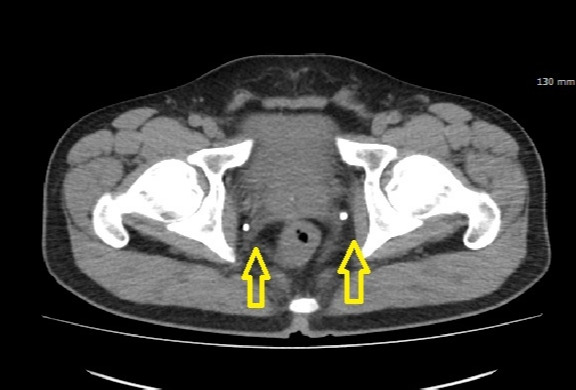

정맥돌 1.jpg 노란 화살표가 가리키는 것이 골반 내 존재하는 정맥돌들이며 요관 결석과 매우 혼동됨

정맥돌은 특히 골반 내 정맥에서 자주 발견된다. 골반은 남성의 경우 방광과 전립선, 여성의 경우 방광과 자궁이 위치한 해부학적 공간으로, 심장에서 멀고 좌식 생활 등으로 인해 정맥 순환이 쉽게 저하되는 부위이다. 특히 장시간 앉아 있는 자세는 골반 내 정맥을 기계적으로 압박하여 혈류의 정체를 유발할 수 있고, 이로 인해 형성된 혈전이 석회화되면서 정맥돌(phlebolith)이 발생할 가능성이 커진다. 이러한 조건은 정맥 순환의 지연과 더불어 결정 형성을 촉진할 수 있는 환경을 만든다.